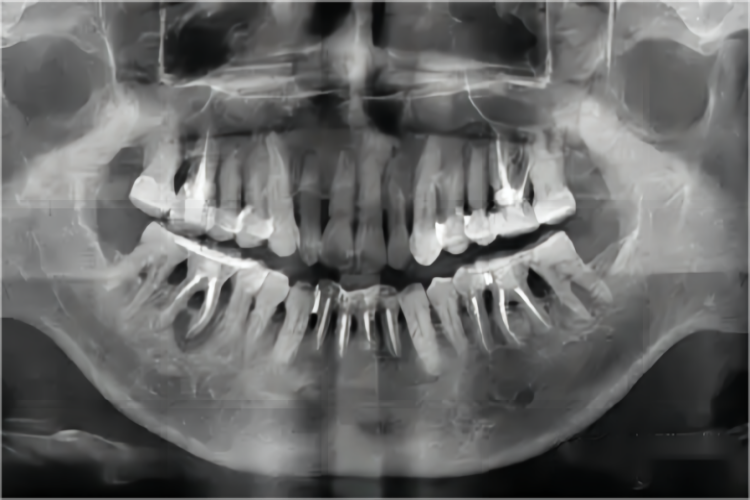

水平型吸收是常见的牙槽骨吸收方式,X线片影像学表现为牙槽间隔、唇颊侧或舌腭侧牙槽骨从嵴顶往根尖方向呈横向的高度减低,吸收程度比较均匀一致,形成骨上袋。垂直型吸收也称角形吸收,表现为局部牙槽骨或牙槽间隔的一侧,沿牙体长轴自冠方斜向根端吸收,与牙根面之间形成一定角度的骨缺损,最终造成牙槽骨吸收。